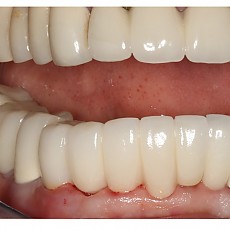

시술전후사진 12 페이지

Total 189건 12 페이지